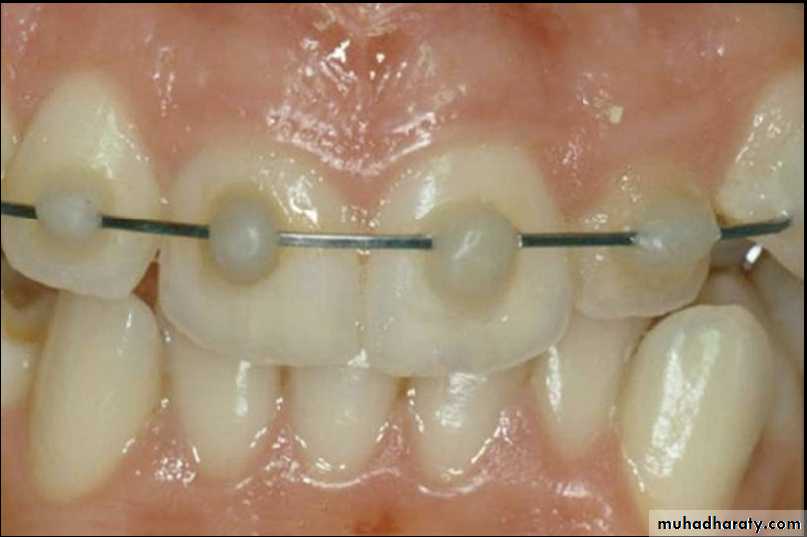

Fixation by wiring

Composite and orthodontic wire splint

Position of teeth after digital reduction and stabilization with bonded arch wire.- Intrusion